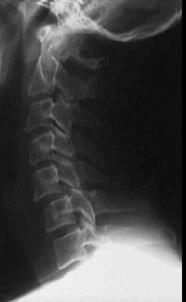

TRAUMA CERVICALA

Incidenta laterala Incidenta

laterala Incidenta

Aspect normal Imagine

incompleta Aspect

normal